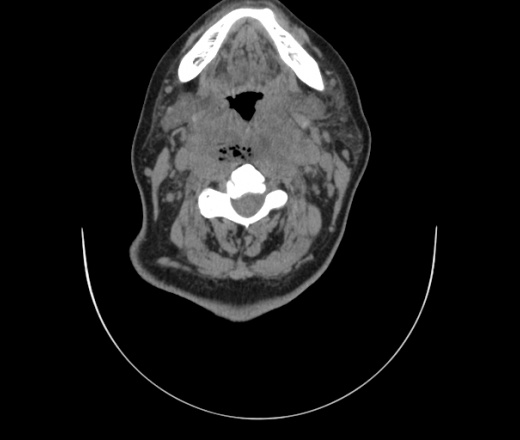

Женщина поступила в х/о спустя 4 дня после того как при употреблении карася подавилась костью.

Наличие газа в средостении на протяжении тел С2-С6 (медиастинальна эмфизема); рыбная кость на уровне тела С6.

При всем уважении, но говорить о медиастинальной эмфиземе, оценивая мягкие ткани шеи, как-то слишком резко. На мой взгляд, это ретрофарингеальное пространство.

Эвакуировали почти 100мл гноя. Но кость не смогли найти. Думаю что она даст дальнейшее ослоднение. Эндоскопически за черпалонадгортаной звязкой не смогли зайти в пищевод, все мягкие ткани отечные, просвет пищевода сдавлен. По всей видимости параэзофагеальная клетчака тоже задействована. Эмпиема, если ее можно так назвать, незнаю как правильно дошла до уровня яремной вырезки. Чем закончиться напишу. Ждем медиастинита.

Флегмона заглоточного пространства шеи, только операция, флегмоны вскрывают. Риск медиастинита.

Согласен с Вами; конечно, наличие газа в клетчатке ретрофарингеального пространства (затмение с опечаткой..). К сожалению, процесс "продвигается" к медиастиниту. Но почему никто, не отмечает наличие рыб. кости; или это для Всех очевидно?

Так вы уже отметили. Хотя ориентировал бы не скелетотопически, а на перстнечерпаловидный сустав.

Кость то мы сразу выявили, размеры где то 17*2мм, но ее так и не получается найти в этой каше